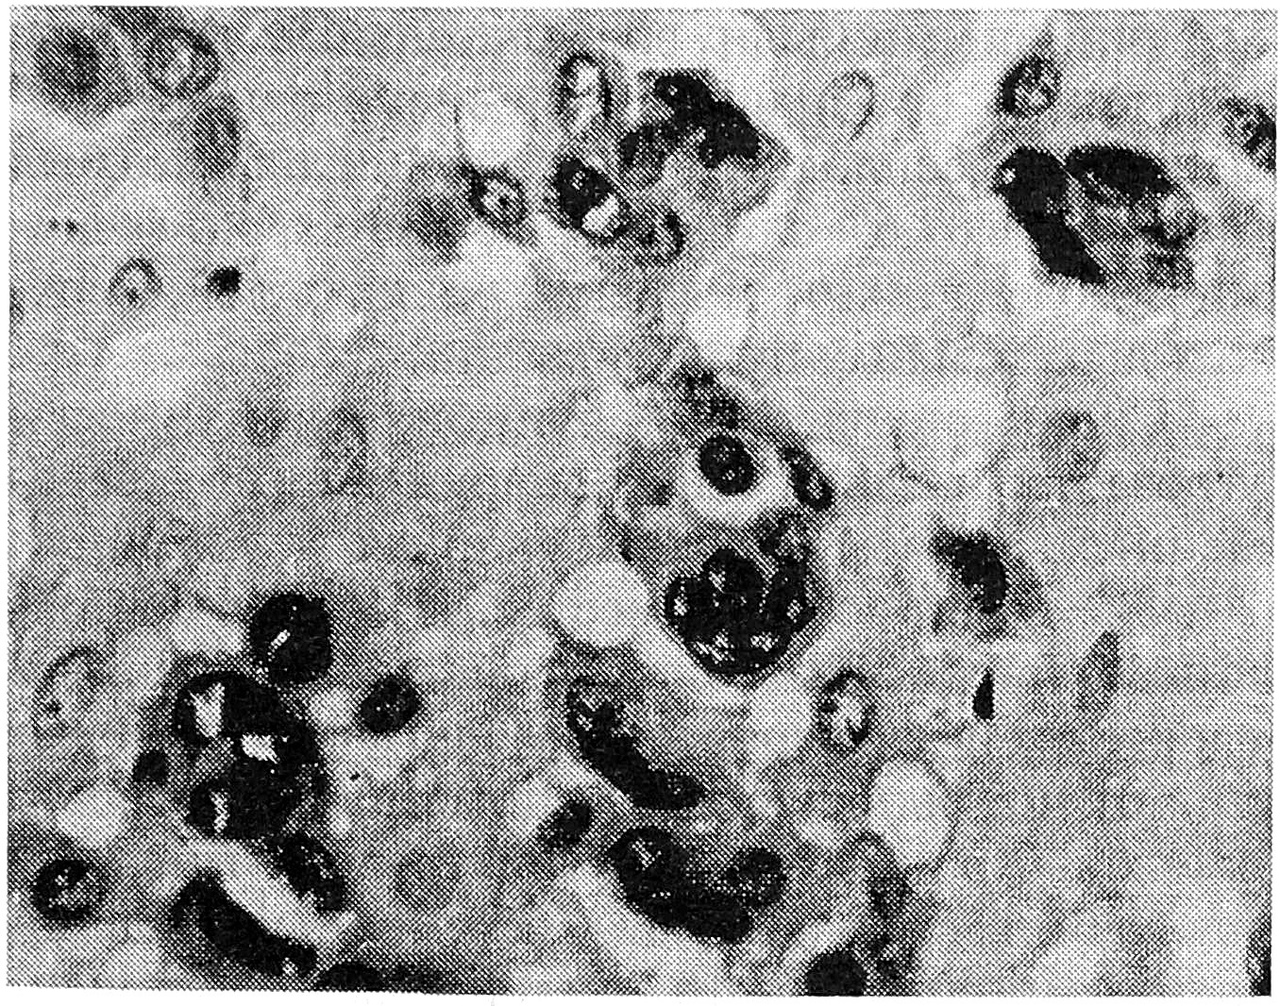

Рис. 3. Артериосклероз и почти полное закрытие просвета сосудов в средних ворсинах, очаговый продуктивный виллузит при уреаплазмозе. х 100.

У тех женщин 1-й группы, у которых в качестве возбудителя была идентифицирована уреаплазма, отсутствовали тяжелые формы базального децидуита и относительно низкой была частота отечного синдрома (не более чем в 30% случаев). В то же время отмечалось появление в подавляющем большинстве случаев артериосклероза в средних ворсинах (рис. 3) с присоединением в отдельных плацентах продуктивного виллузи- та и продуктивного васкулита в опорных ворсинах. В половине наблюдений была установлена выраженная гиперемия в сосудах терминальных ворсин с бедным содержанием синцитиальных почек на их поверхности, у остальных — гиперпластический тип терминальных ворсин (строма богата клеточными элементами) с недостаточной их васкуляризацией, но с компенсаторным увеличением числа синцитиальных почек. В большей части случаев в плаценте имели место мелкие и редкие кальцификаты. Создается впечатление, что при инфицировании уреаплазмой доминируют сосудистая патология плаценты и стромальная реакция ворсин. Своеобразие хламидийной инфекции заключалось в том, что вне зависимости от степени лимфоцитарной инфильтрации decidua basalis (от легкой до умеренной) к отечному синдрому, частота которого достигала почти 100%, в половине случаев присоединялись кровоизлияния и крупные петрификаты в базальной пластинке. Одновременно известковые отложения имели место и в ворсинах парабазальной зоны (рис. 4). Наиболее ярким и постоянным признаком была выраженная гиперемия ворсин, иногда с явлениями стаза в парабазальной зоне; в 2 случаях выявлен ангиоматоз ворсин (рис. 5). В трети наблюдений обнаружены значительные фибриноидные отложения в базальной пластинке, межворсинчатом пространстве или на поверхности ворсин (чаще в субхориальной зоне), что в 3 случаях осложнилось развитием крупных очагов белых инфарктов. Атрофические и дистрофические изменения синцитиотрофобласта на поверхности терминальных ворсин в 50% наблюдений сочетались с умеренной гиперплазией синцитиальных почек. Обращали на себя внимание вакуольная дистрофия цитотрофобласта, отек амниона в плодных экстраплацентарных оболочках и гладком хорионе.